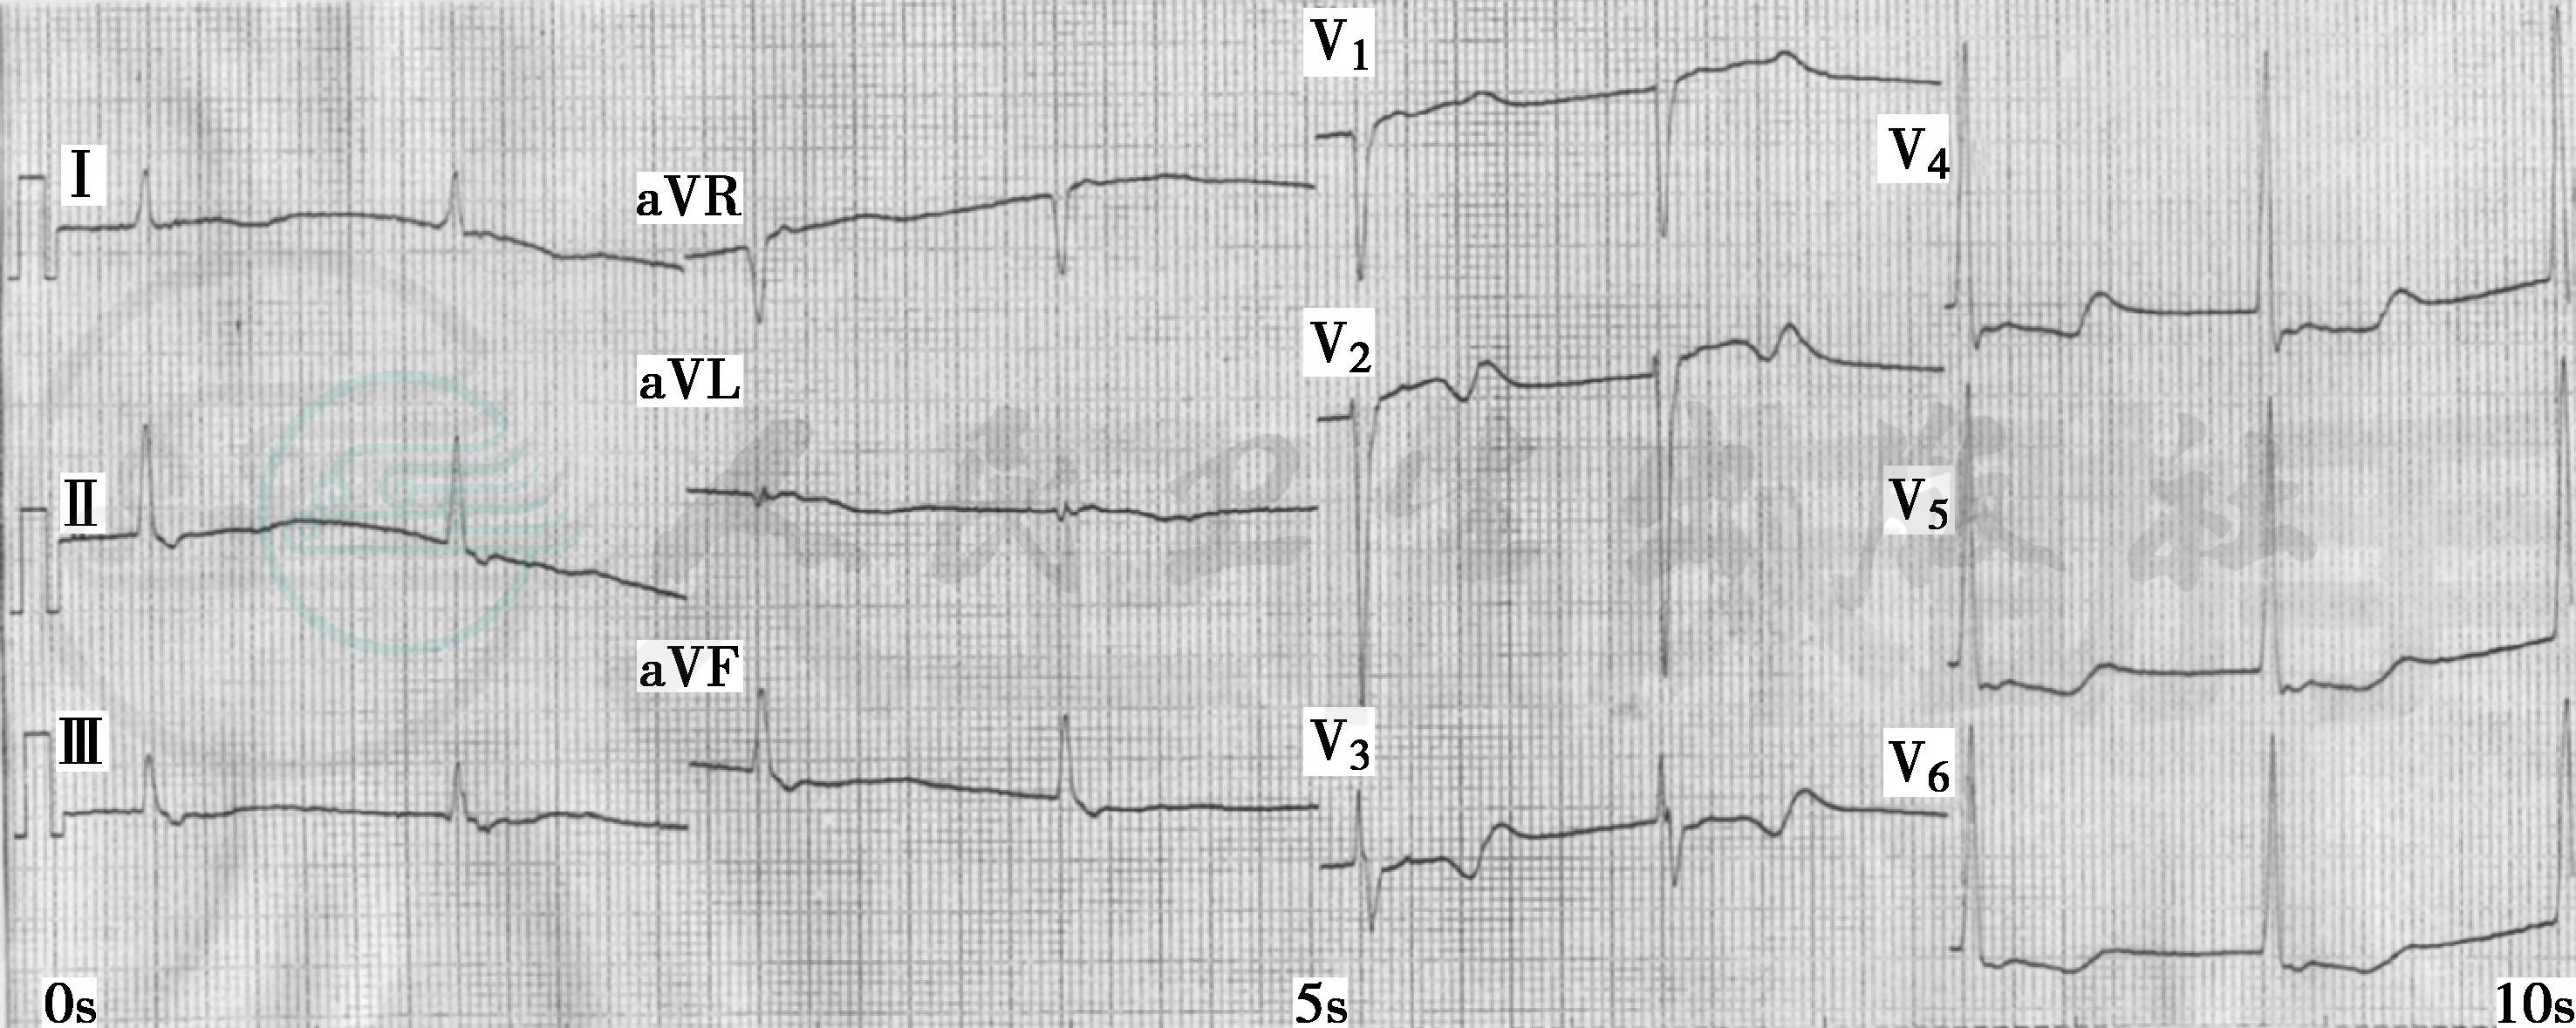

血、尿、便常规无异常。肌钙蛋白T<0.03ng/ml。生化:空腹血糖6.75mmol/L,LDL 3.45mmol/L,TC 5.79mmol/L,血钾3.2mmol/L,补钾2日后复查血钾正常。心脏彩超:LAD 47mm,LVD 58mm,EF 35%,左心房、左心室增大;左心室运动幅度减弱;左心室舒张及收缩功能减低;彩色血流未见异常。心电图检查见图1~图3。

图1 入院心电图:窦性心律,Ⅱ、Ⅲ、aVF、V3~V6导联T波低平、倒置